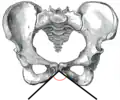

Angle sous-pubien féminin

Angle sous-pubien masculin